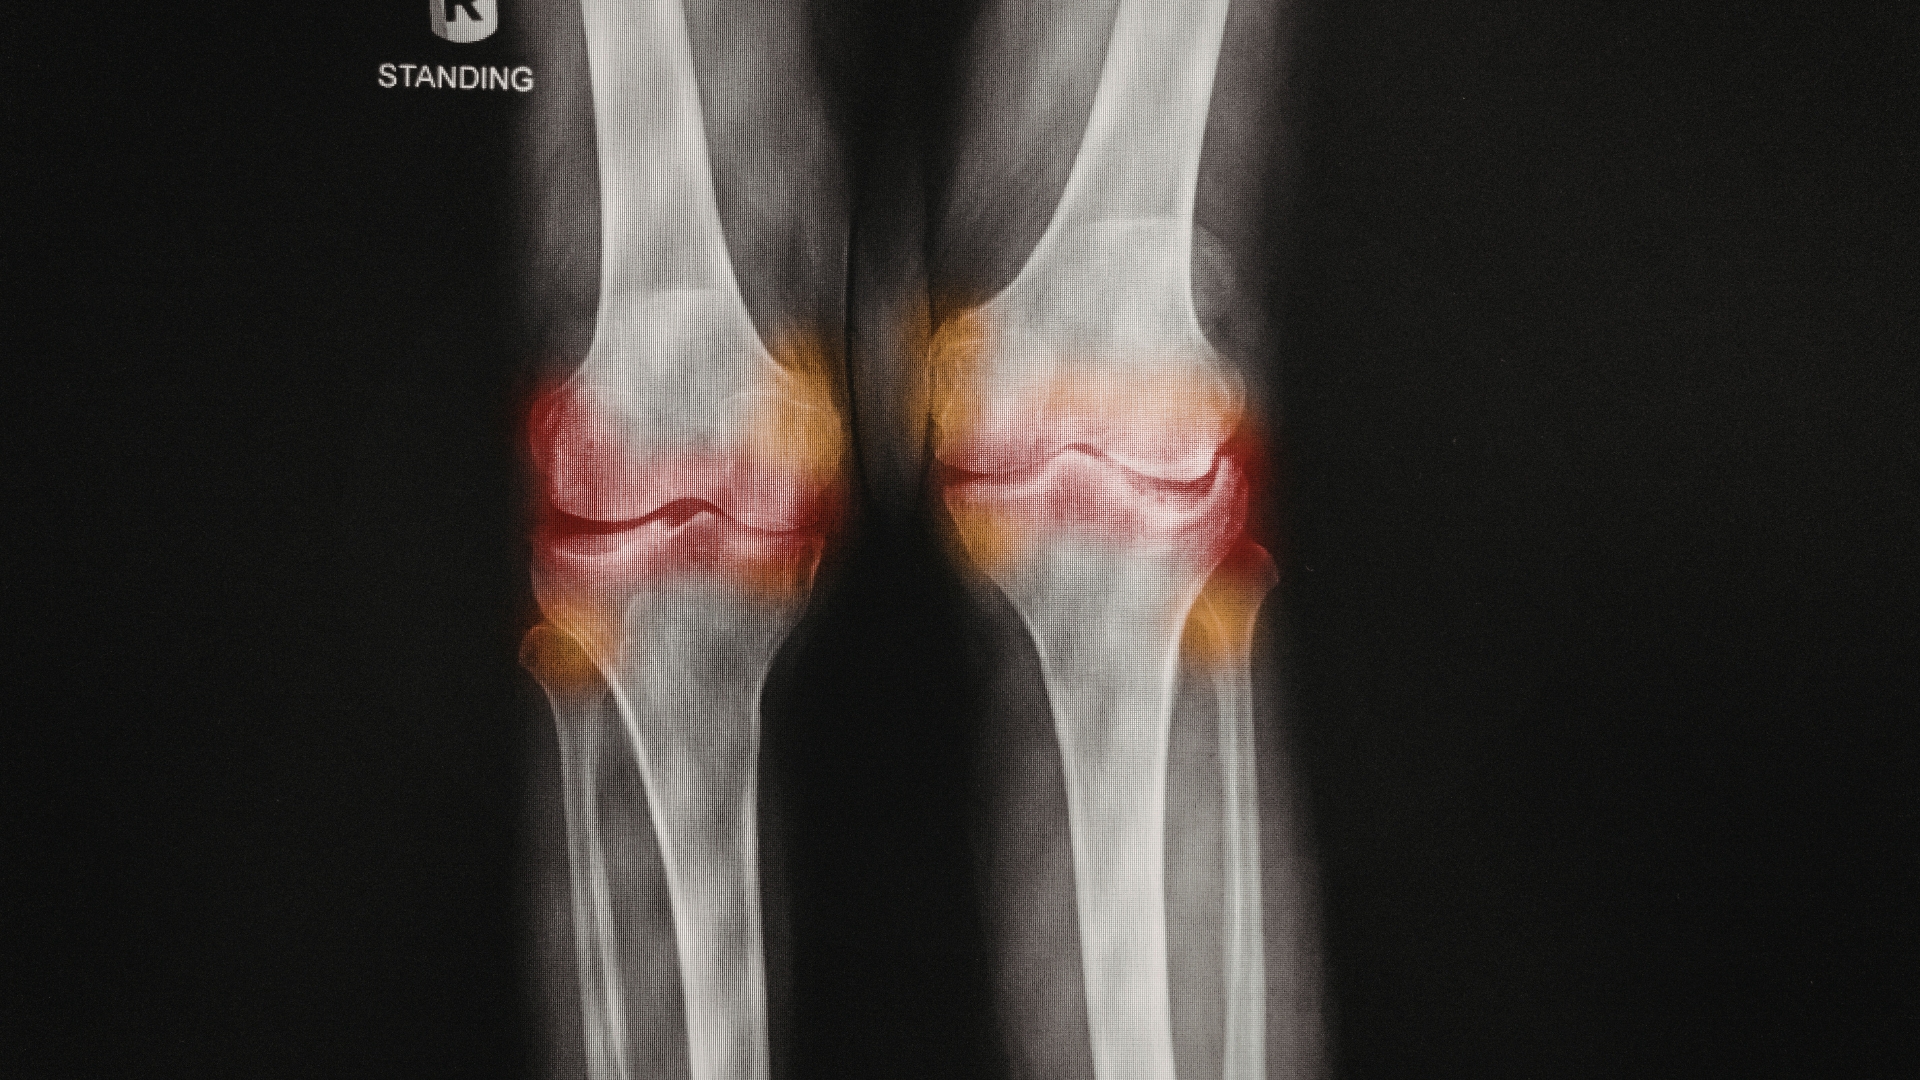

Ở người lớn tuổi, đau gối mạn tính thường liên quan đến thoái hóa khớp. Phim X-quang giúp đánh giá mức độ hẹp khe khớp, sự hình thành gai xương và biến đổi bề mặt xương theo thời gian. Những thông tin này có giá trị trong việc lựa chọn hướng điều trị như dùng thuốc giảm đau, tập phục hồi chức năng hoặc cân nhắc can thiệp phẫu thuật khi cần.

Tư thế chịu lực (đứng): Thường áp dụng khi đánh giá thoái hóa khớp, giúp nhận biết mức độ hẹp khe khớp khi khớp chịu trọng lượng cơ thể.